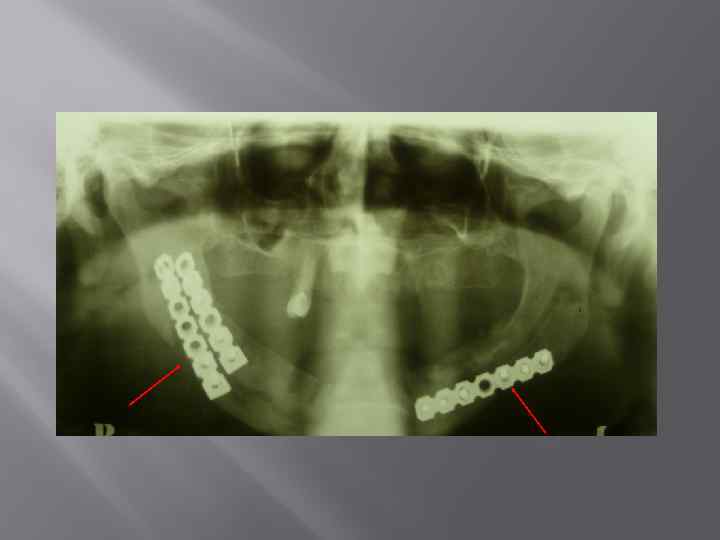

Деструктивная форма хронического остеомиелита нижней челюсти.

Деструктивная форма хронического остеомиелита (гнездная форма)